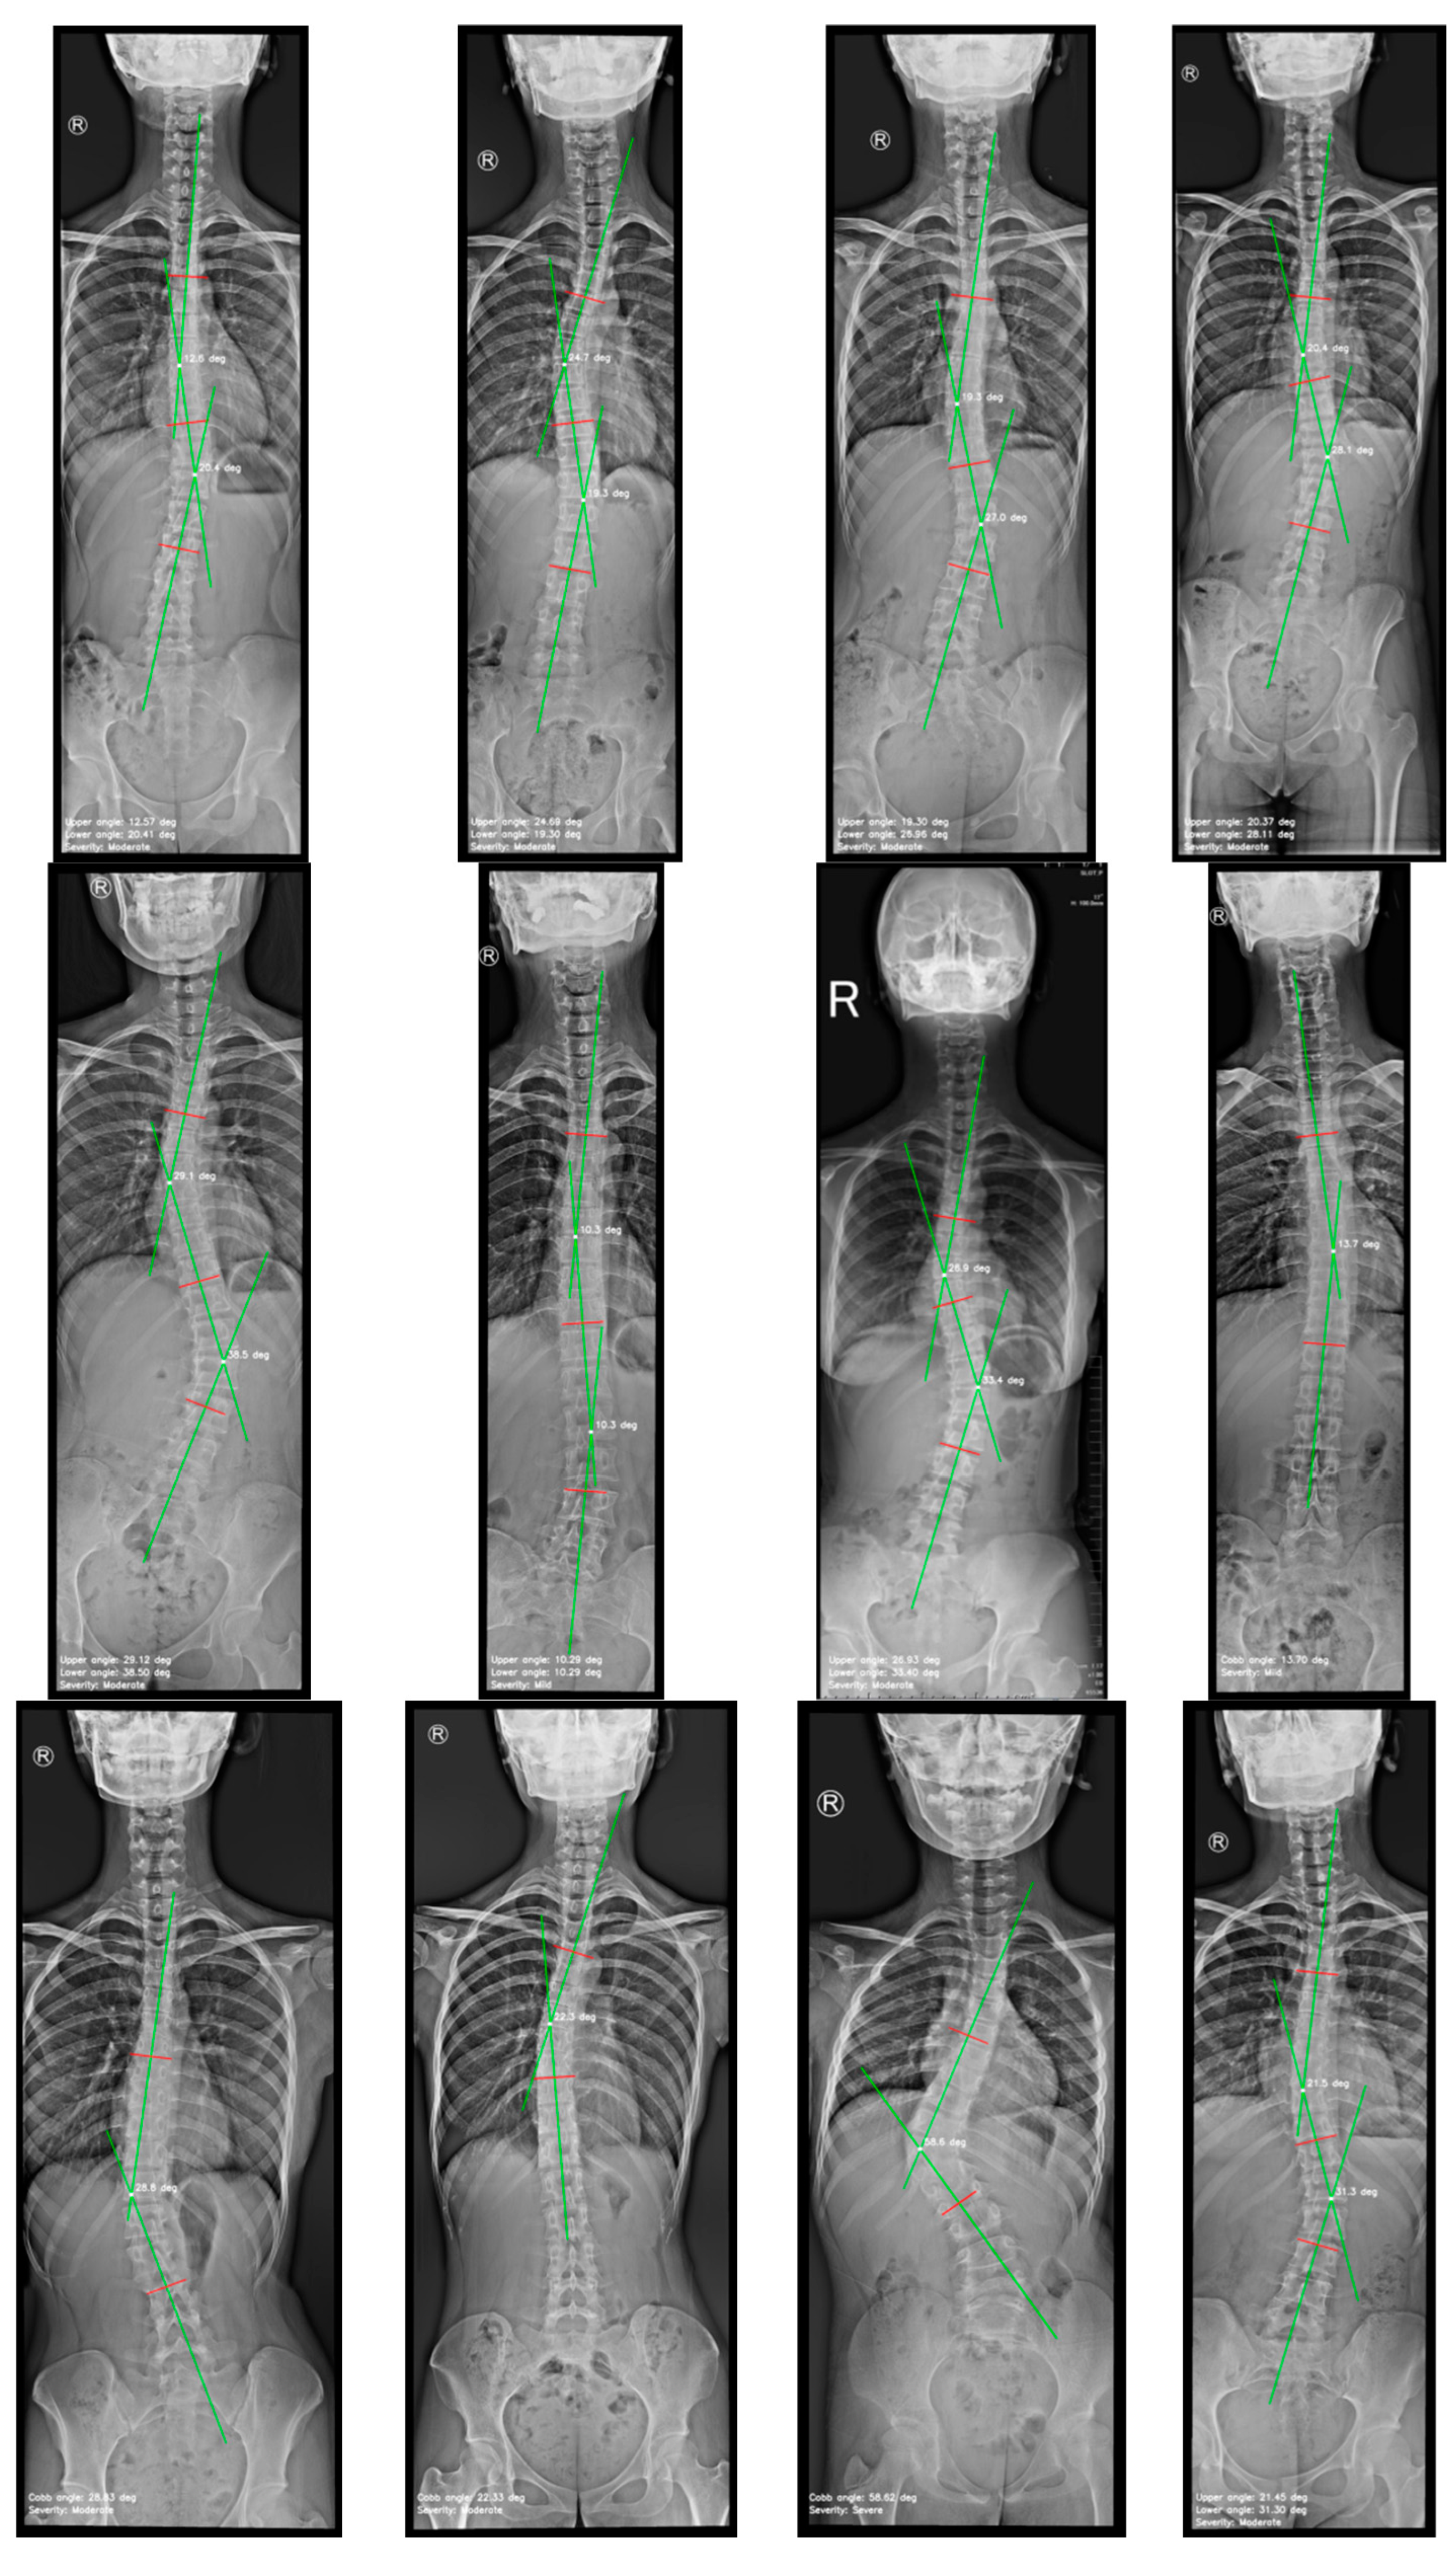

4.1. Instance Segmentation

4.2. Cobb Angle Measurement

| Cobb angle measurements | Mean ± Standard deviation (range) |

|---|---|

| Manual measurement by observer A | 25.43° ± 10.85° (range 11.50-54.00°) |

| Manual measurement by observer B | 25.89° ± 10.00° (range 10.00-53.00°) |

| Measured by the automated method | 26.69° ± 12.50° (range 10.29-59.34°) |

| Analysis | ICC (95% CI) | MAD ± SD | MAE ± SD |

|---|---|---|---|

| Observer A vs. observer B | 0.939 (0.868, 0.971) | 3.31º ± 1.56º | 3.31° ± 1.53° |

| Observer A vs. automated | 0.961 (0.926, 0.984) | 2.54º ± 2.10º | 2.54° ± 2.06° |

| Observer B vs. automated | 0.895 (0.780, 0.950) | 4.07º ± 3.29º | 4.07° ± 3.22° |

| Overall: Observer A & B vs. automated | 0.928 (0.853, 0.967) | 3.31º ± 2.69º | 2.96° ± 2.60° |